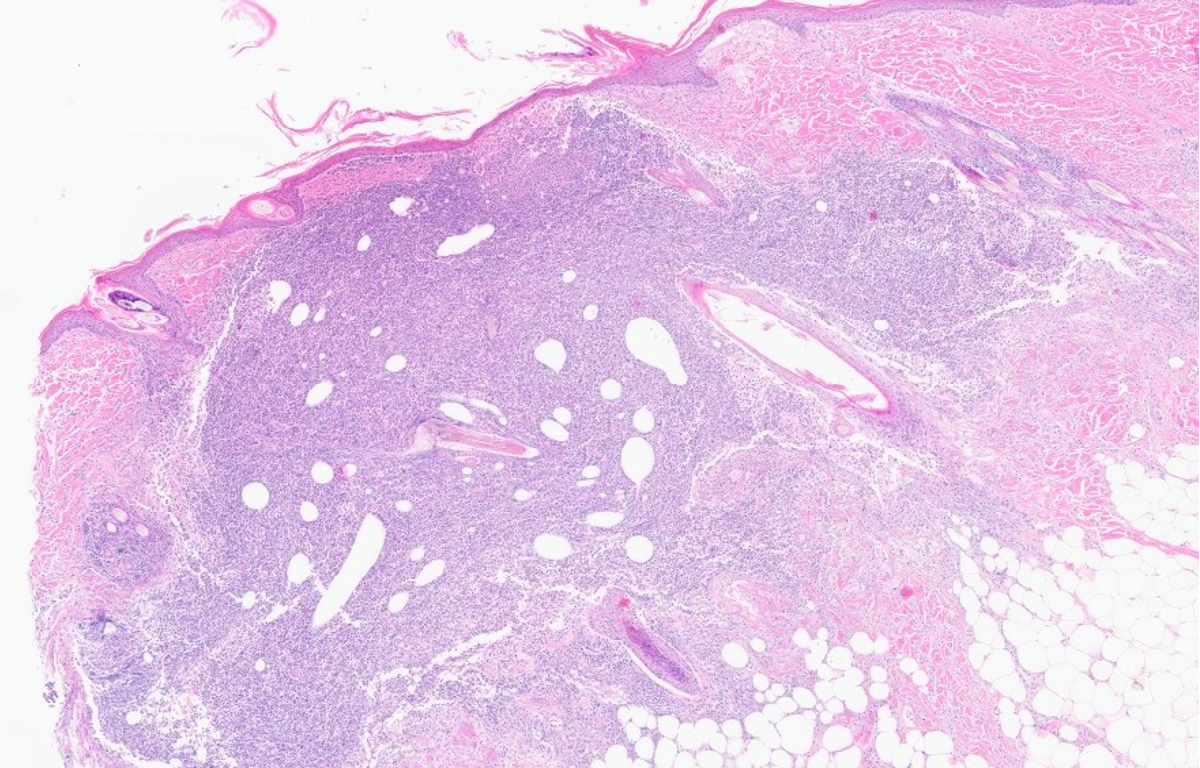

How does sarcoptic mange present histologically?

Intra-lesional mites and ova present (not as good as doing a scrape)

Severe epidermal hyperplasia

Ortho and patchy para keratosis

Spongiosis

Inflammatory infiltrate within epidermis and eosinophilic pustules